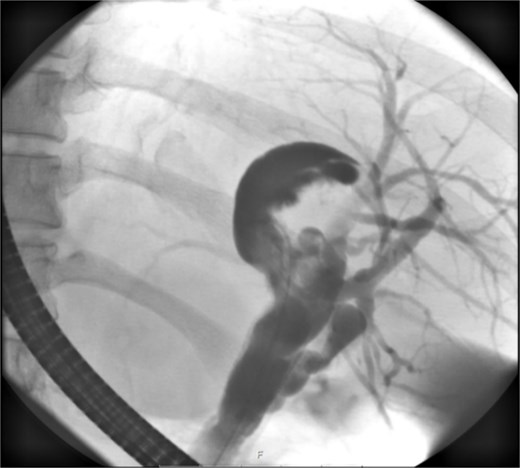

Endoscopic retrograde cholangiopancreatography (ERCP) confirmed communication between the dilated bile ducts and the lesion in the left hepatic lobe (Fig. 3). There were no signs of biliary obstruction or extrahepatic involvement. Based on the suspicion of malignancy and the localized nature of the lesion, surgical intervention was planned.

ERCP reveals a crescent-shaped, contrast-enhancing structure (40 mm in length) originating from the left hepatic duct.